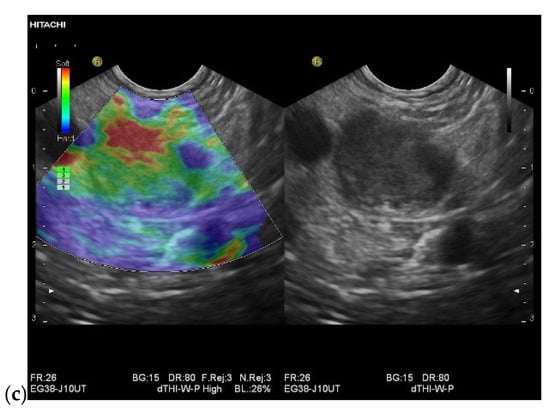

3.4. CEUS and CH-EUS

| Colour Doppler Imaging | RCC metastases are hypervascularized Most other pancreatic metastases are hypovascularized | No hypervascularization | Hypervascularized |

| Elastography (small lesions up to 15 mm) [67] | 41% softer or isoelastic, 59% stiffer compared to pancreatic parenchyma | 4% soft or isoelastic, 96% stiffer compared to pancreatic parenchyma | 64% soft or isoelastic, 36% stiffer compared to pancreatic parenchyma |

| Cases | CEUS | CH-EUS | ||

|---|---|---|---|---|

| Arterial Phase | Venous Phase | Arterial Phase | Venous Phase | |

| RCC metastases [83] (n = 4) | Hyperenhancement, Early | Hyperenhancement | ||

| RCC metastases [61] (n = 3) | Hyperenhancement, homogeneous pattern | Slow washout | ||

| RCC metastasis [86] (n = 1) | Hyperenhancement, Inhomogeneous pattern | No washout | ||

| Melanoma metastasis [63] (n = 1) | Iso- to slightly hypoenhanced | Hypoenhanced | ||

| Melanoma metastasis [87] (n = 1) | Isoenhanced | Hypoenhancement of the peripheral rim, central non-enhancement | ||

| Melanoma metastasis [61] (n = 1) | Isoenhanced, heterogeneous | Fast washout | ||

| SCLC metastasis [83] (n = 1) | Hyperenhancement | Rapid washout | ||

| Breast, ovarian, colon metastases, sarcoma metastases [61] (n = 6) | Hypoenhancement, homogeneous or heterogeneous | Fast or slow washout | ||

| Lymphoma metastasis [61] (n = 1) | Hyperenhancement, homogeneous pattern | Fast washout |